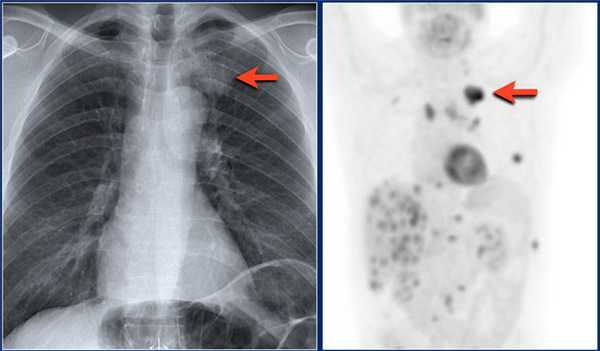

![ra69]()

Очаги, которые не реагируют на лечение антибиотиками, наиболее точным неинвазивным методом исследования является ПЭТ/КТ.

ПЭТ/КТ позволяет обнаружить злокачественный узел с чувствительностью 97% и специфичностью 78%. Ложно-положительные результаты присутствуют также, но при случаях хронической гранулематозной болезни и ревматоидном артрите. Ложно-отрицательные результаты бывают при низко дифференцируемых опухолях таких, как карциноид и альвеолярно-клеточном раке размером менее 1 см.

![ra70]()